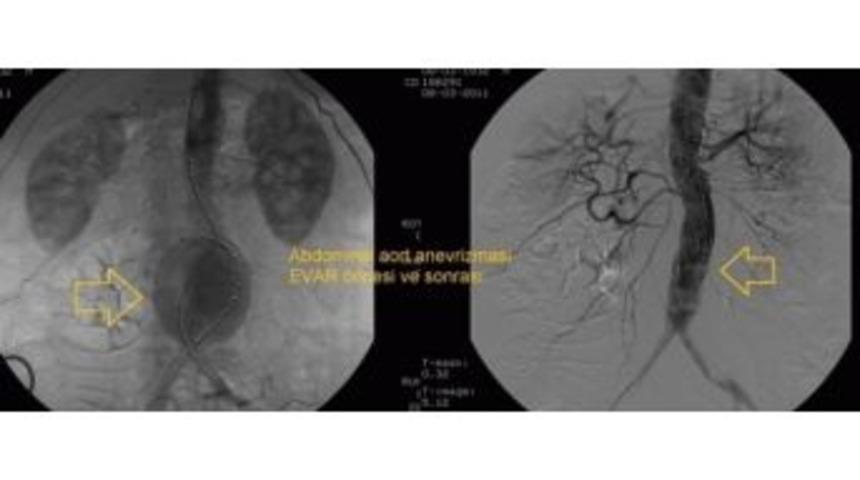

Aort Damarındaki Genişleme İçin "evar" Tedavisi